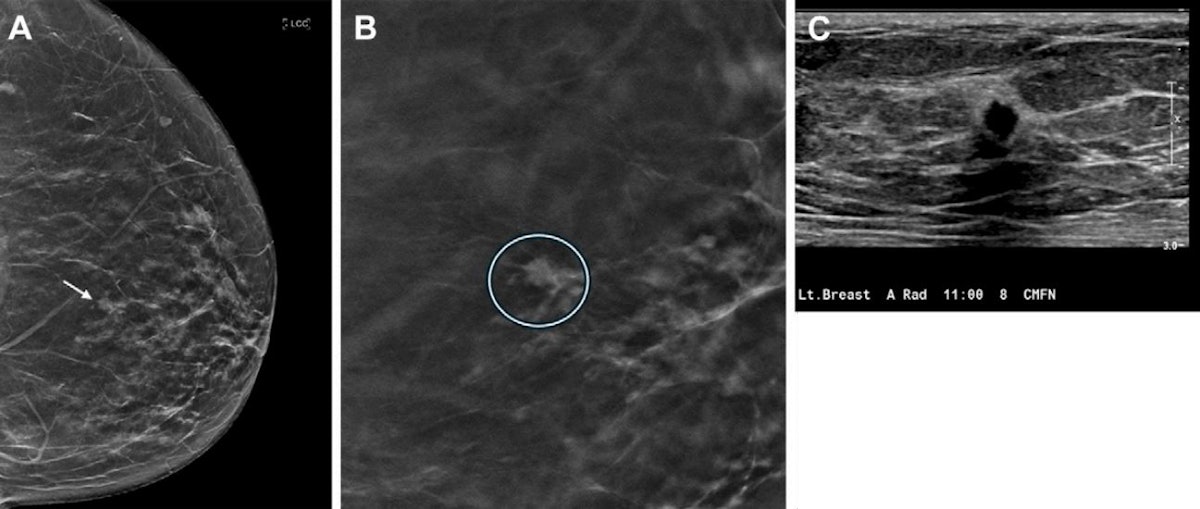

HOT ! 健康・医学 Breast Cancer DBT increases cancer detection over 10-year period | AuntMinnie

• DBT increases cancer detection over 10-year period | AuntMinnie